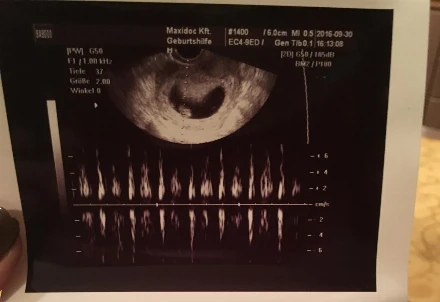

Terhesnapló10 - Liza: Dobog a szíve! (8. hét)

Elmentünk az első kontroll vizsgálatra a szülészorvosunkhoz. Furcsa találkozás volt. Én úgy mentem oda, hogy előtte egyeztettem az asszisztenssel, minden információt megosztottam vele (mikor volt az utolsó menstruációm, hány éves vagyok, akarom-e...